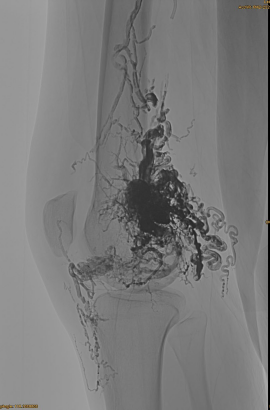

Hastanın temel bilgileri: kadın, 36 yıl; AVM pelvis, kalça, diz, sol OSG, çoklu pre - embolizasyonları.

Kullanılan ürünler: 3pcs lava-34,14pcs lav-18.

İlk DSA:

Nihai Sonuç:

Neredeyse hiç venöz çıkış:

Geç aşama, başka bir embo gerekli, ama çok daha iyi: